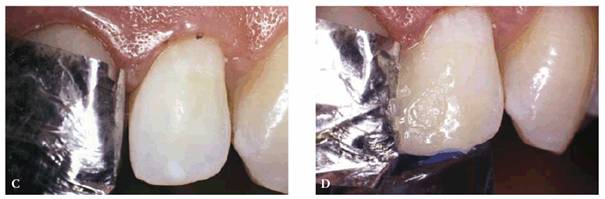

TREATMENT: To maximize longevity and esthetics, porcelain laminates were

chosen as the most conservative treatment. Figure 23-14B shows the previously bonded left central

incisor coated with dentin-disclosing solution to determine how much enamel was

left. The tooth is washed, leaving red dye to indicate dentin areas (see Figure 23-14C). Figure 23-14D shows the left central incisor laminate being bonded

into place. Figure 23-14E shows the occlusal view, indicating just how

much the left central incisor protruded before restoration. Four porcelain

laminates were used to create a symmetric arch with proper spacing (see Figure 23-14F). The improvement by the final result can be

Figure 23-14B: Dentin disclosing solution is applied to determine how much enamel remained on this previously bonded left central incisor.

Figure 23-14C: Red dye indicates the areas of dentin.

Figure 23-14D: A porcelain laminate is bonded to the left central incisor.

Figure 23-14E: This before occlusal view shows how much the left central incisor protruded prior to treatment.